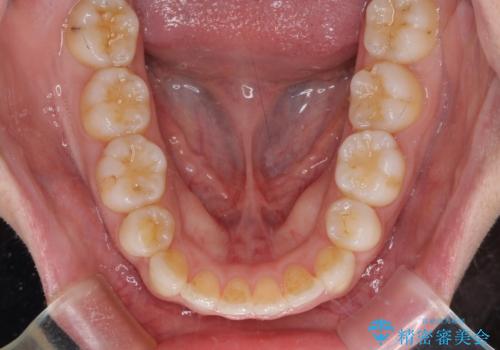

叢生が強かったため、口元の突出感の改善には限界がありましたが、横側からも口元が引っ込んだ感じが分かるほど改善されました。